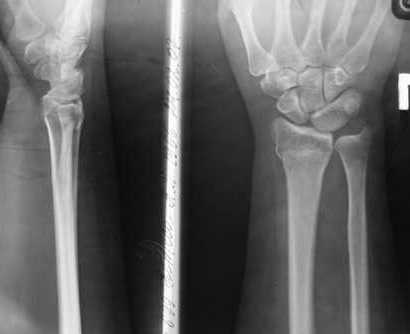

Уважаемые коллеги, обращаюсь к вашему опыту. Обратилась женщина 45лет, профессия - швея, травма 24.02.07 вколоченный перелом правого луча (см Ргр )

на Ргр нарастают явления остеопороза, не смотря на прием препаратов кальция.

AL> на Ргр нарастают явления остеопороза, не смотря на прием

AL> препаратов кальция(рис.

Видимо там был оскольчатый перелом луча и шиловидного отростка

локтевой кости.

В гипсовом повязке наблюдалось вторичное смещение костных отломков по длине (при передне-заднем рентгенограмме), и при боковй проекции видно смещение отломка в дорсальном направлении и таким

образом последный дает компрессию нервов в лучезапястном канале (типа синд. Зудека)